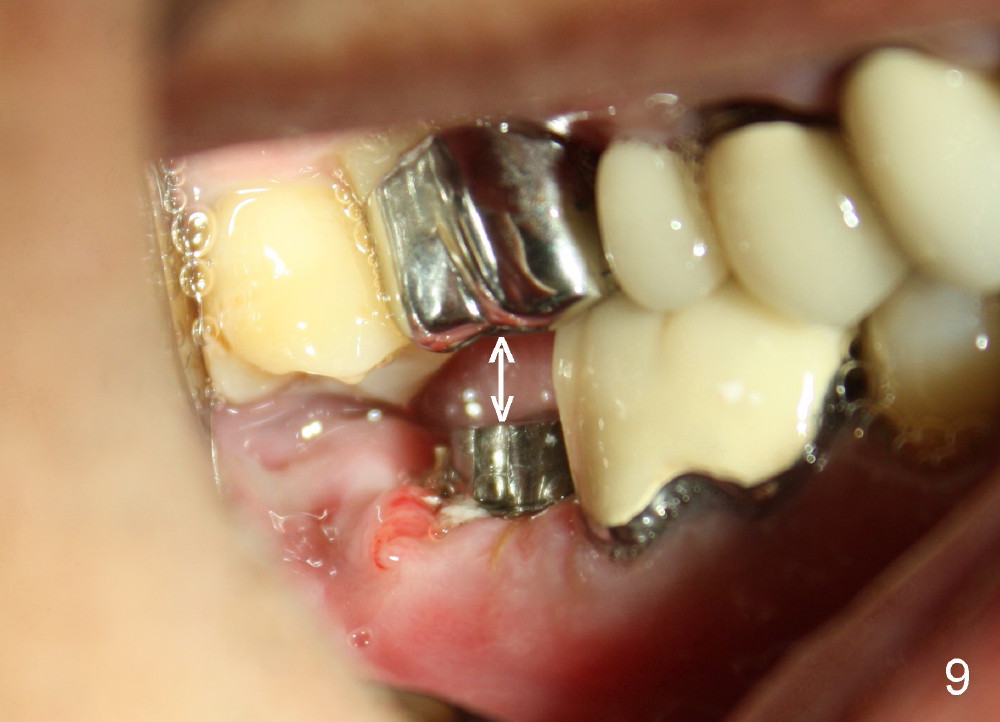

A 51-year-old man has experienced pain and swelling in the lower right 2nd molar for 7 months (Fig.1, P: post in the mesial root; <: gutta percha inserted into a buccal fistula). Fig.2 is taken immediately before extraction (<: purulent discharge from the mesiobuccal fistula) and immediate implant (Fig.3 implant design: 7x14 mm). A vertical root fracture is noted in the mesial root (Fig.4: lingual view). The septum is in fact absent, as compared to Fig.1. The mesiobuccal plate is low; the osteotomy starts lingual to the center of the socket. Fig.5 shows a 4.5x17 mm tap in place: approximately 3.5 mm in the new bone (~2.5 mm from the inferior alveolar canal). When a 7x17 mm tap (14 mm from the gingival margin) is placed in the socket, it looks relatively small. Fig.6 shows a 8x14 mm implant in place with a small gap distally. Mineralized cancellous allograft and Osteogen mixture is placed mainly buccally, followed by a thin strip of collagen dressing and sutures (Fig.7); an abutment (A) is placed to keep perio dressing in place. The perio dressing does not stay long. The buccal portion dislodges by itself 5 days postop. The lingual portion is removed in clinic. New dressing is going to be re-applied, because the buccal wound has not completely healed (Fig.8 <, albeit asymptomatic) with partial exposure of the bone graft (*). Why is the dressing lost so early? The abutment is not long enough; there is plenty of occlusal clearance (Fig.9 arrows). A longer abutment is used to increase mechanical retention for perio dressing (Fig.10). By the time the second perio dressing dislodges, the wound has healed (Fig.11, 13 days postop).

Fig.12 show root fracture associated with mesiobuccal post of the 2nd molar. In contrast the lower right 2nd premolar is intact without crown after root canal therapy. It appears that the post weakens the root.